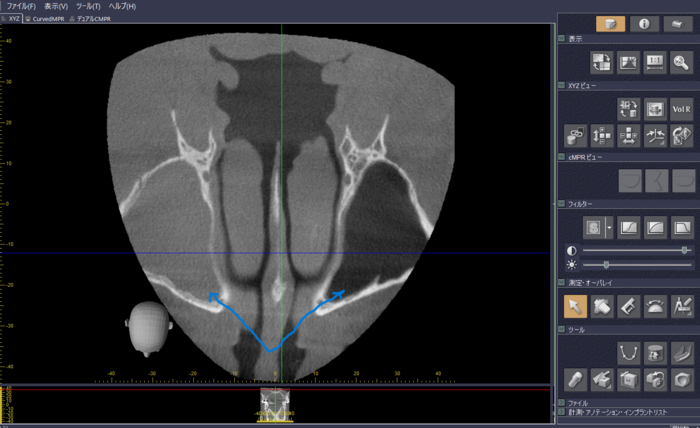

図2は、矢印が左右の上顎洞(副鼻腔の一つ)を示していますが、左側は白くなっています。炎症がないものは右側のように黒く見えるのですが、炎症があると白く見えます。果たしてこの炎症はどこから来ているのか探ってみると、右上の一番奥の歯の神経が死んでしまって、それが原因で右側の上顎洞が炎症を起こしています。図3では、矢印の部分が上顎同に通じているように見えます。このように鼻の病気でも歯が原因の場合も考えられるので、CT撮影は有効な診断基準になります。

上 図2:下 図3